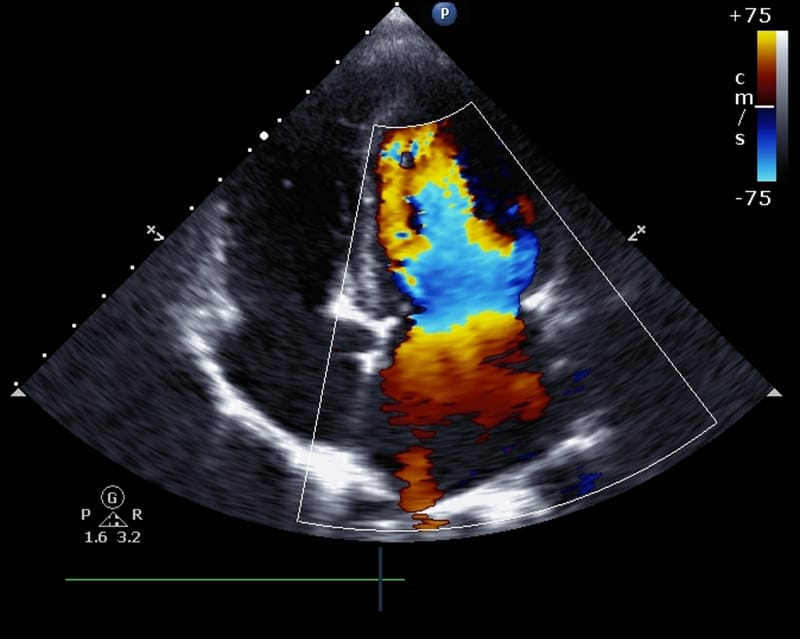

Ultrasound images of your heart are taken to assess cardiac function